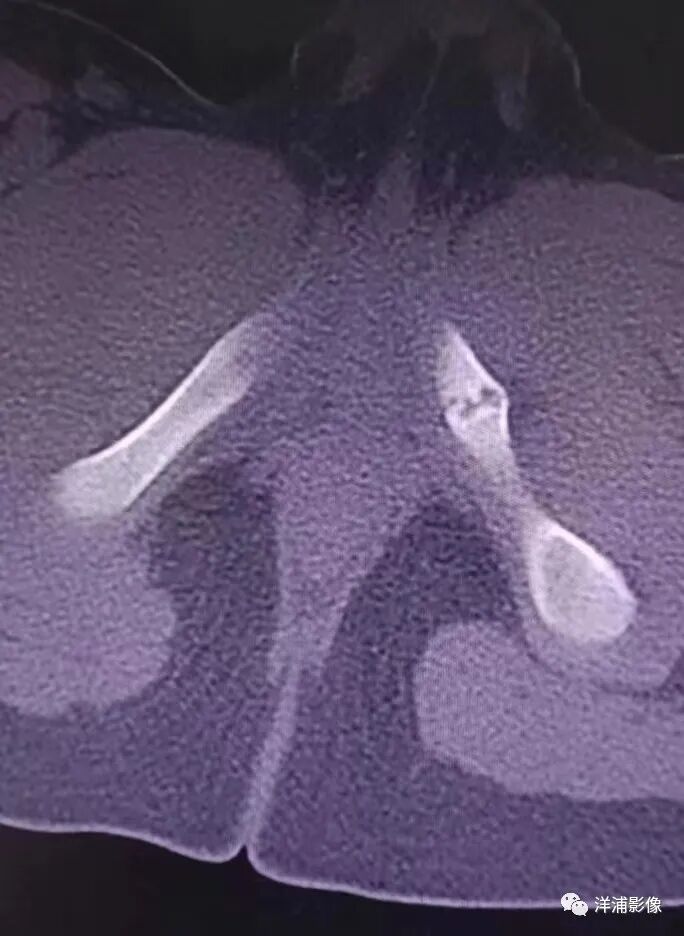

病史:男孩,8岁,外伤来诊,发现左侧坐骨异常;

左侧坐骨锯齿状改变,骨折?

CT:CT具有高密度分辨力和横断面成像特点并可三维重建,可见坐骨耻骨结合处局限性膨大,有破碎,其内有低密度透光区,边缘不规则,骨质断裂不连接,骨髓腔有硬化变现。无明显的死骨和骨膜反应,邻近的软组织正常。